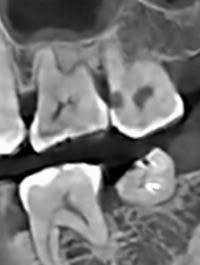

XQuang trước – sau điều trị

Việc quan sát đúng cách có thể giúp loại bỏ sâu răng đầy đủ. Ba điều kiện thiết yếu cần đạt được trong quá trình phẫu thuật để có thể quan sát đúng cách nhằm ngăn ngừa việc loại bỏ men răng/ngà răng không đủ trong quá trình chuẩn bị khoang: (i) trường phẫu thuật thông thoáng, (ii) kiểm soát độ ẩm chặt chẽ và (iii) độ phóng đại phù hợp. Cần có trường phẫu thuật thông thoáng trước khi can thiệp phẫu thuật. Loại bỏ mảng bám, mảnh vụn và cao răng trên/dưới nướu là điều cần thiết. Ngoài ra, để đảm bảo tổn thương có lỗ rỗng và cải thiện khả năng tiếp cận bằng thị giác, việc tách răng bằng cách đặt một dụng cụ tách đàn hồi chỉnh nha trong một tuần để tạo ra một khoảng cách nhỏ ở kẽ răng là rất hữu ích. Kiểm soát độ ẩm thông qua việc sử dụng đê cao su rất hữu ích cho việc phục hồi chất lượng cao. Ngoài ra, sử dụng kính lúp phóng đại giúp giảm tình trạng nhô ra ở rìa răng tới 40%. Tình trạng nhô ra có thể ảnh hưởng đến việc đánh giá kết quả lâm sàng của phục hồi trong các lần tái khám do gây ra sự hiểu sai về lý do thất bại. Thất bại của phục hồi có thể là do nhô ra và rò rỉ thay vì do chính đường hầm. Các phương pháp tiếp cận trái ngược khác để tạo điều kiện loại bỏ sâu răng đầy đủ bao gồm tăng kích thước của đường tiếp cận nhai và áp dụng kiểm tra chụp X quang. Tuy nhiên, việc tăng kích thước của quá trình chuẩn bị đường hầm sẽ làm giảm khả năng chống gãy của răng. Một nghiên cứu đã báo cáo rằng ngay cả việc kiểm tra chụp X quang tại chỗ trong quá trình chuẩn bị đường hầm cũng không thể làm tăng hiệu quả của việc loại bỏ sâu răng. Người ta cho rằng không nên coi chụp X-quang là công cụ chẩn đoán phù hợp để xác định sâu răng trong quá trình chuẩn bị đường hầm.

Một cân nhắc khác là tình trạng xâm lấn hoặc kích ứng tủy sống trong quá trình chuẩn bị hoặc phục hồi đường hầm. Để tránh lộ tủy, cần tiến hành kiểm tra tiền phẫu cẩn thận với sự hỗ trợ của phim chụp X-quang. Hướng của mũi khoan phải được kiểm soát tốt với phim chụp X-quang làm tham chiếu. Để tránh kích ứng tủy trong quá trình phẫu thuật hoặc do vật liệu phục hồi, nên sử dụng lớp lót thủy tinh ionomer biến tính bằng nhựa hoặc canxi hydroxylate để che tủy gián tiếp nếu đường hầm đóng kín với tủy răng. Lớp lót này không chỉ đóng vai trò là hàng rào bảo vệ tủy mà còn tăng cường quá trình tái khoáng hóa của ngà răng bị sâu.